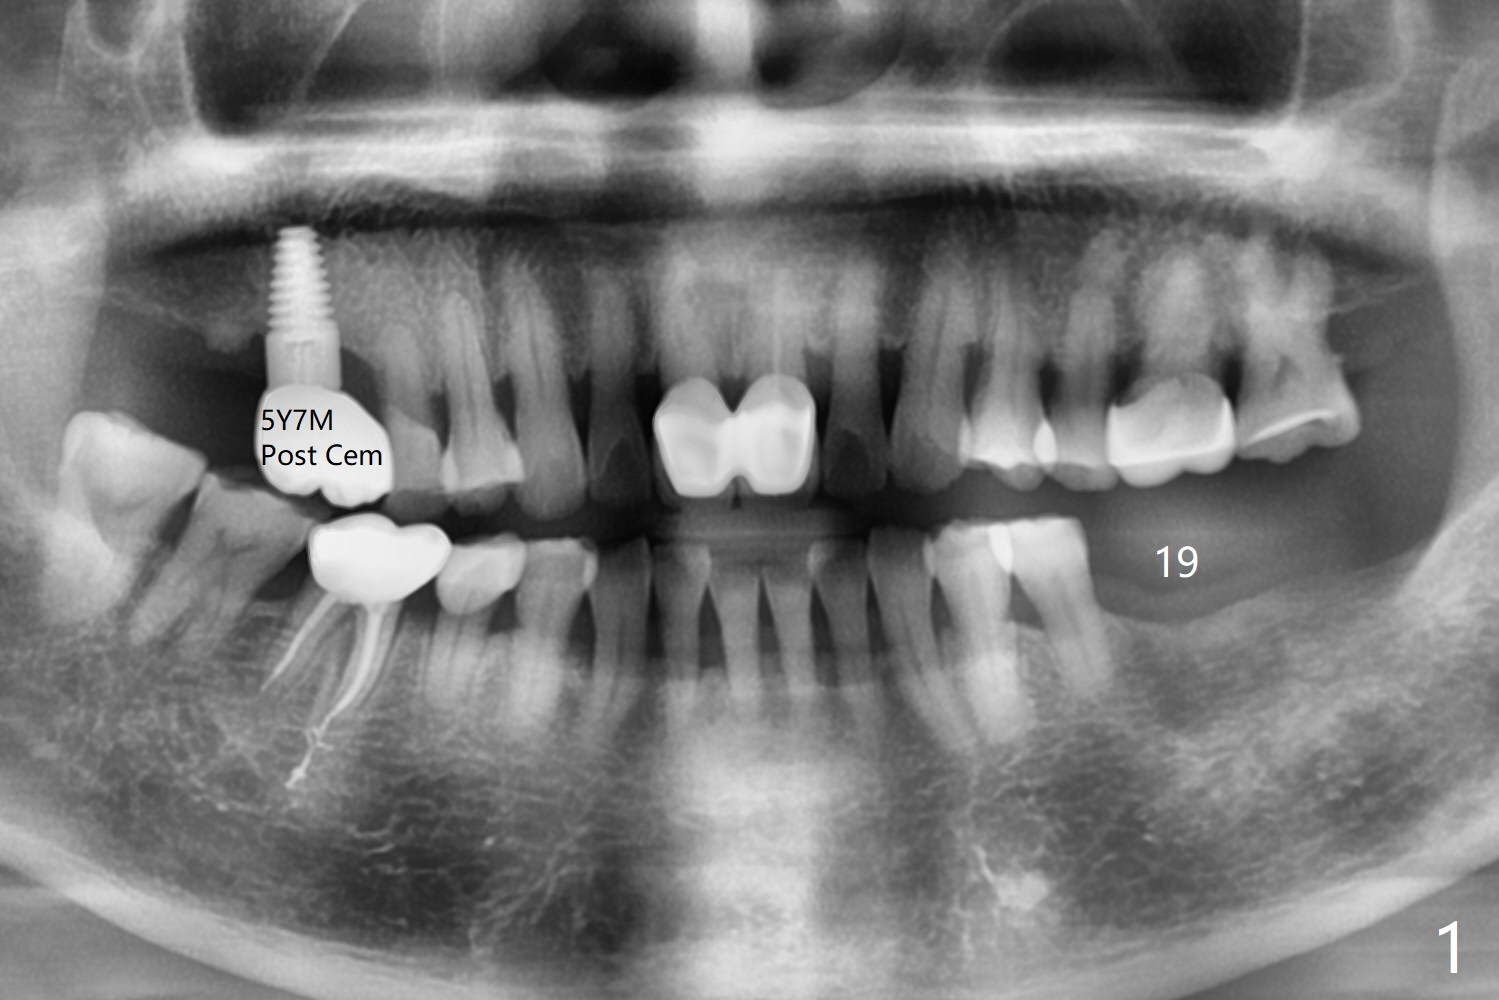

A 74-year-old woman returns for #19 implant consul-tation 5 years 7 months post cementa-tion at #3 (Fig.1). Since the implant at #3 (6x14 mm) has less ideal trajectory associated with free hand placement (Fig.3 (mild distolingual (L) thread exposure; Fig.1,4 (distal placemennt), guide will be fabricated for #19 implant placement. The lingual plate is thick and dense (Fig.2 L). To prevent drill and implant deviation buccally, a 5x11.5 mm implant will be placed as lingual as possible. A 5 mm cortical drill will be used before 2.2-4.5 mm ones being used for depth. The 4.0 mm drill will reach the final depth (apical underprep). A 17 mm long tissue-level implant will be placed. 17-5.5=11.5 mm (thread portion); 1.2 mm drill tip for the rough surface. Prepare 3.5x14 or 17 mm dummy implant to test the depth.